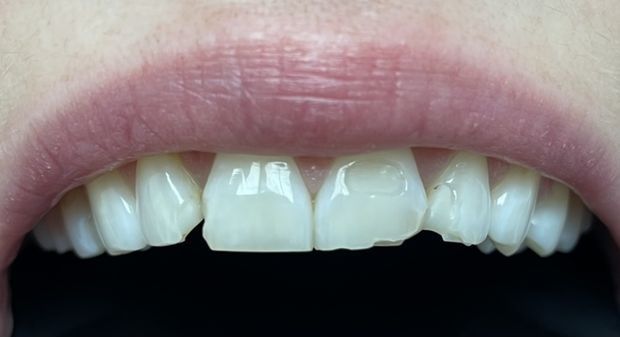

W tym przypadku zniszczonych i krótkich koron wykonano zabieg chirurgicznego wydłużenia koron klinicznych z plastyką dziąseł oraz wykonano pojedyncze korony cyrkonowe licowane porcelaną w kolorze BL2.